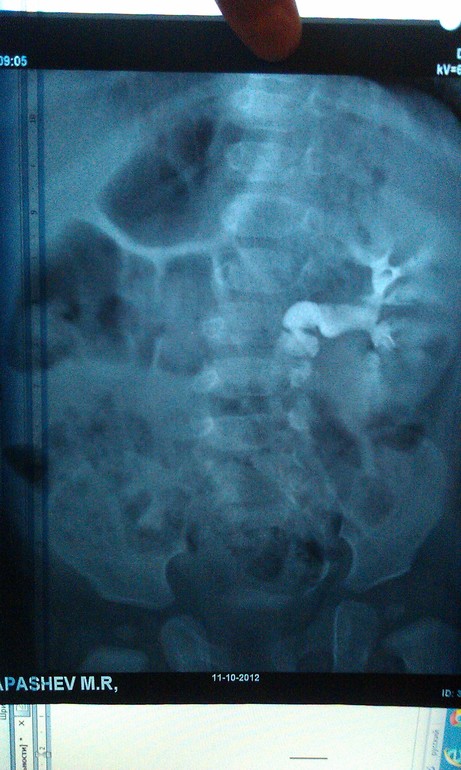

Урография

Максиим Викторович. Если возможно, могли бы вы прокомментировать нашу урограмму. Заключение рентгенологов и урологов разнятся. Хотелось бы послушать мнение третьего специалиста.

Олеся, я бы с радостью, но так снимки объективно оценить не смогу, тем более не зная клинической ситуации. Слева понятно, а с правой почкой что?